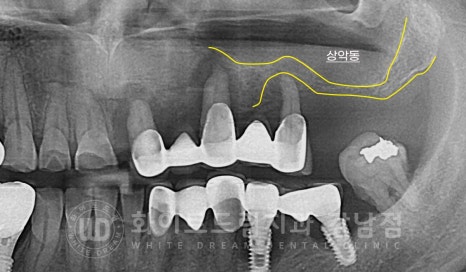

▲ 증상이 더 시급한 20번대 브릿지, 30번대 임플란트 어금니 부위

그럼 치료를 진행한 부위, 20, 30번대 상태는 어땠을까요?

상악 브릿지 치료가 되어 있는 치아 부위는 이미 사용이 불가능할 정도로

염증이 심한 상태였고, 브릿지 통째로 빠질 것처럼 심한 흔들림을 동반하고 있었습니다.

염증이 심한 치아에 발생하는 주 증상 치아 돌출 & 치아 뿌리 노출도 확인되고

이로 인해 교합도 틀어진 상태입니다.

하악 임플란트도 거의 염증이 임플란트를 잡아주고 있는 상태였는데요.